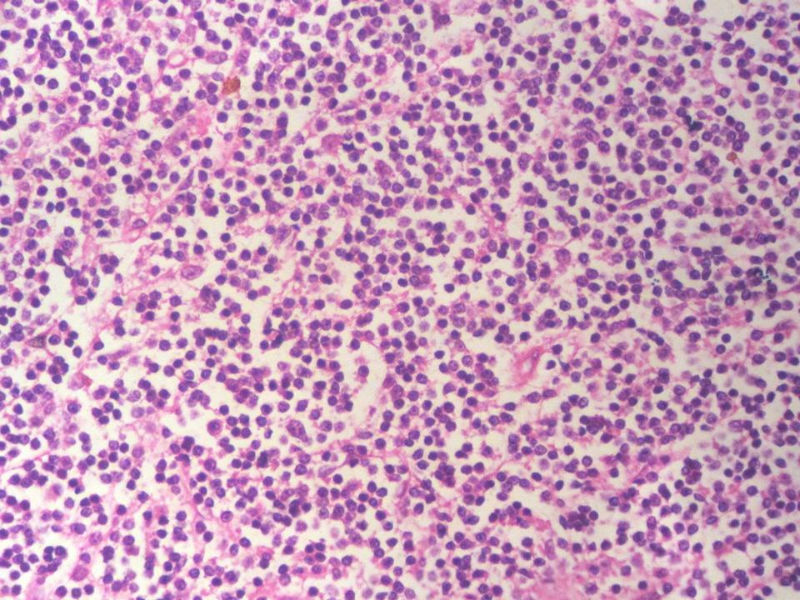

男,49岁,左眼睑球结膜下肿物2个月,手术切除。检查肿块3X2X2厘米,切面灰红色,质软。

本例是发生在特殊部位“结膜下”,HE肿瘤细胞形态形态一致,形似单核样B细胞。B细胞标记若明确阳性,诊断MALT是挺合理的。

HE:  1.MALT粘膜相关淋巴瘤:本例部位很特殊,位于“结膜下”,考虑MALT很合理;但本例镜下细胞形态很一致,诊断MALT是有难度的。

2. SLL小细胞淋巴瘤:就细胞形态而言,有相似之处,考虑SLL也有道理;但如果在没有发现淋巴结,肝,脾,骨髓或外周血具有病变的前题下,原发于结膜的SLL可能是少见的。

3.套细胞淋巴瘤:细胞大小及一致性比较符合;但本例核太规则了,套细胞淋巴瘤很难有这么规则的圆形或椭圆形。

淋巴瘤  细胞小  形态单一  主要考虑小B细胞淋巴瘤

淋巴样细胞。细胞形态单一,细胞小。主要鉴别:

1)粘膜相关淋巴组织淋巴瘤

2)小细胞性淋巴瘤/慢性淋巴细胞性白血病

3)套细胞淋巴瘤

形态结构与细胞大小,似不支持滤泡性淋巴瘤。

请再标记CD20和CD79a!图片中阳性不明确,根据T细胞标记看,应该是B细胞结节。Ki67散而少,不支持低级别滤泡性淋巴瘤,若B细胞弥漫阳性,则是惰性B细胞非霍奇金淋巴瘤,首先考虑套细胞,然后是边缘区淋巴瘤。不做生发中心标记,Bcl-2在小B细胞淋巴瘤分类中无意义。